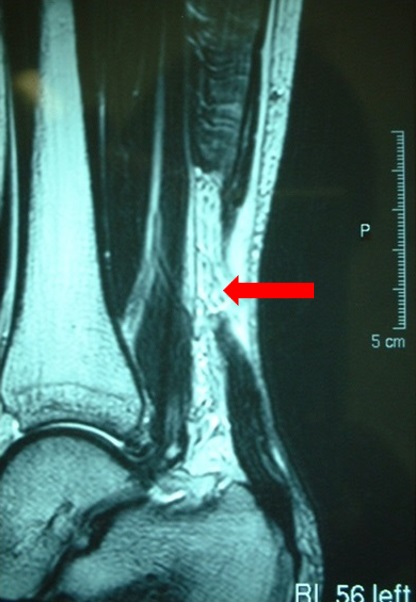

診断は比較的容易で、(1)断裂したアキレス腱部にはっきりした陥凹を触れ(写真1)、(2)つま先立ちが不可能、(3)Thompson testが陽性(ふくらはぎを握っても足首が動かない)、などです。 多くの人が「自分のアキレス腱部に人がぶつかってきた」とか、「ボールが当たった」などの衝撃を感じたり、「ブチッ」と音がしたなどの本人に自覚症状があります。注意点として(1)歩行は可能な場合があり、(2)痛みのない場合があります。最近は超音波検査やMRIにて断裂部を容易に確認できるようになりました(写真2)。

写真2 MRIによるアキレス腱断裂状態(矢印)